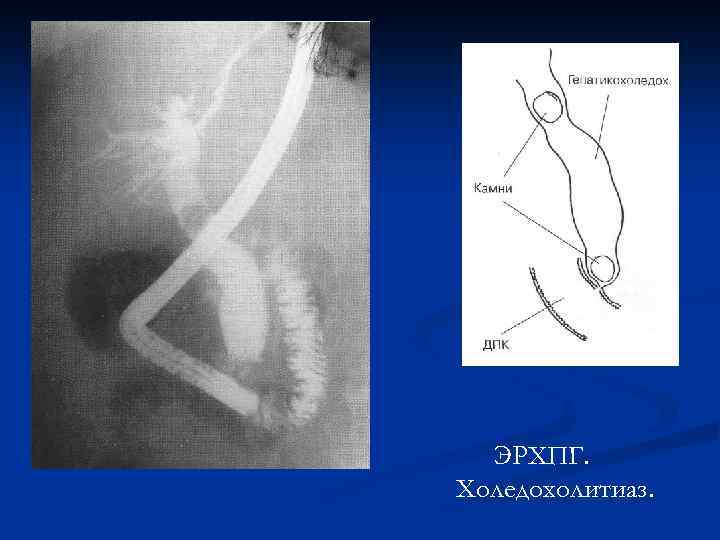

ЭРХПГ. Холедохолитиаз.

ЭРХПГ. Холедохолитиаз.

ЭРХПГ. Холедохолитиаз.

ЭРХПГ. Холедохолитиаз.